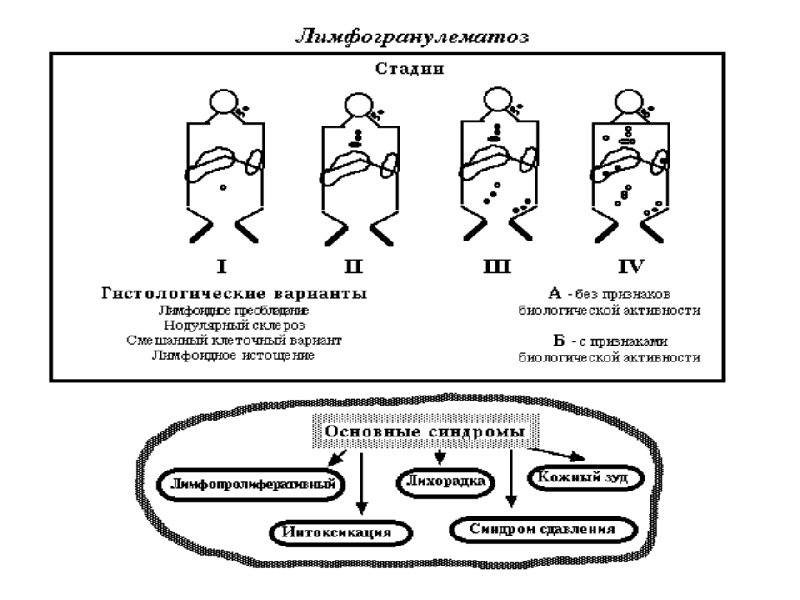

Морфологические варианты лимфогрануломатоза

Схемы химиотерапии лимфогрануломатоза